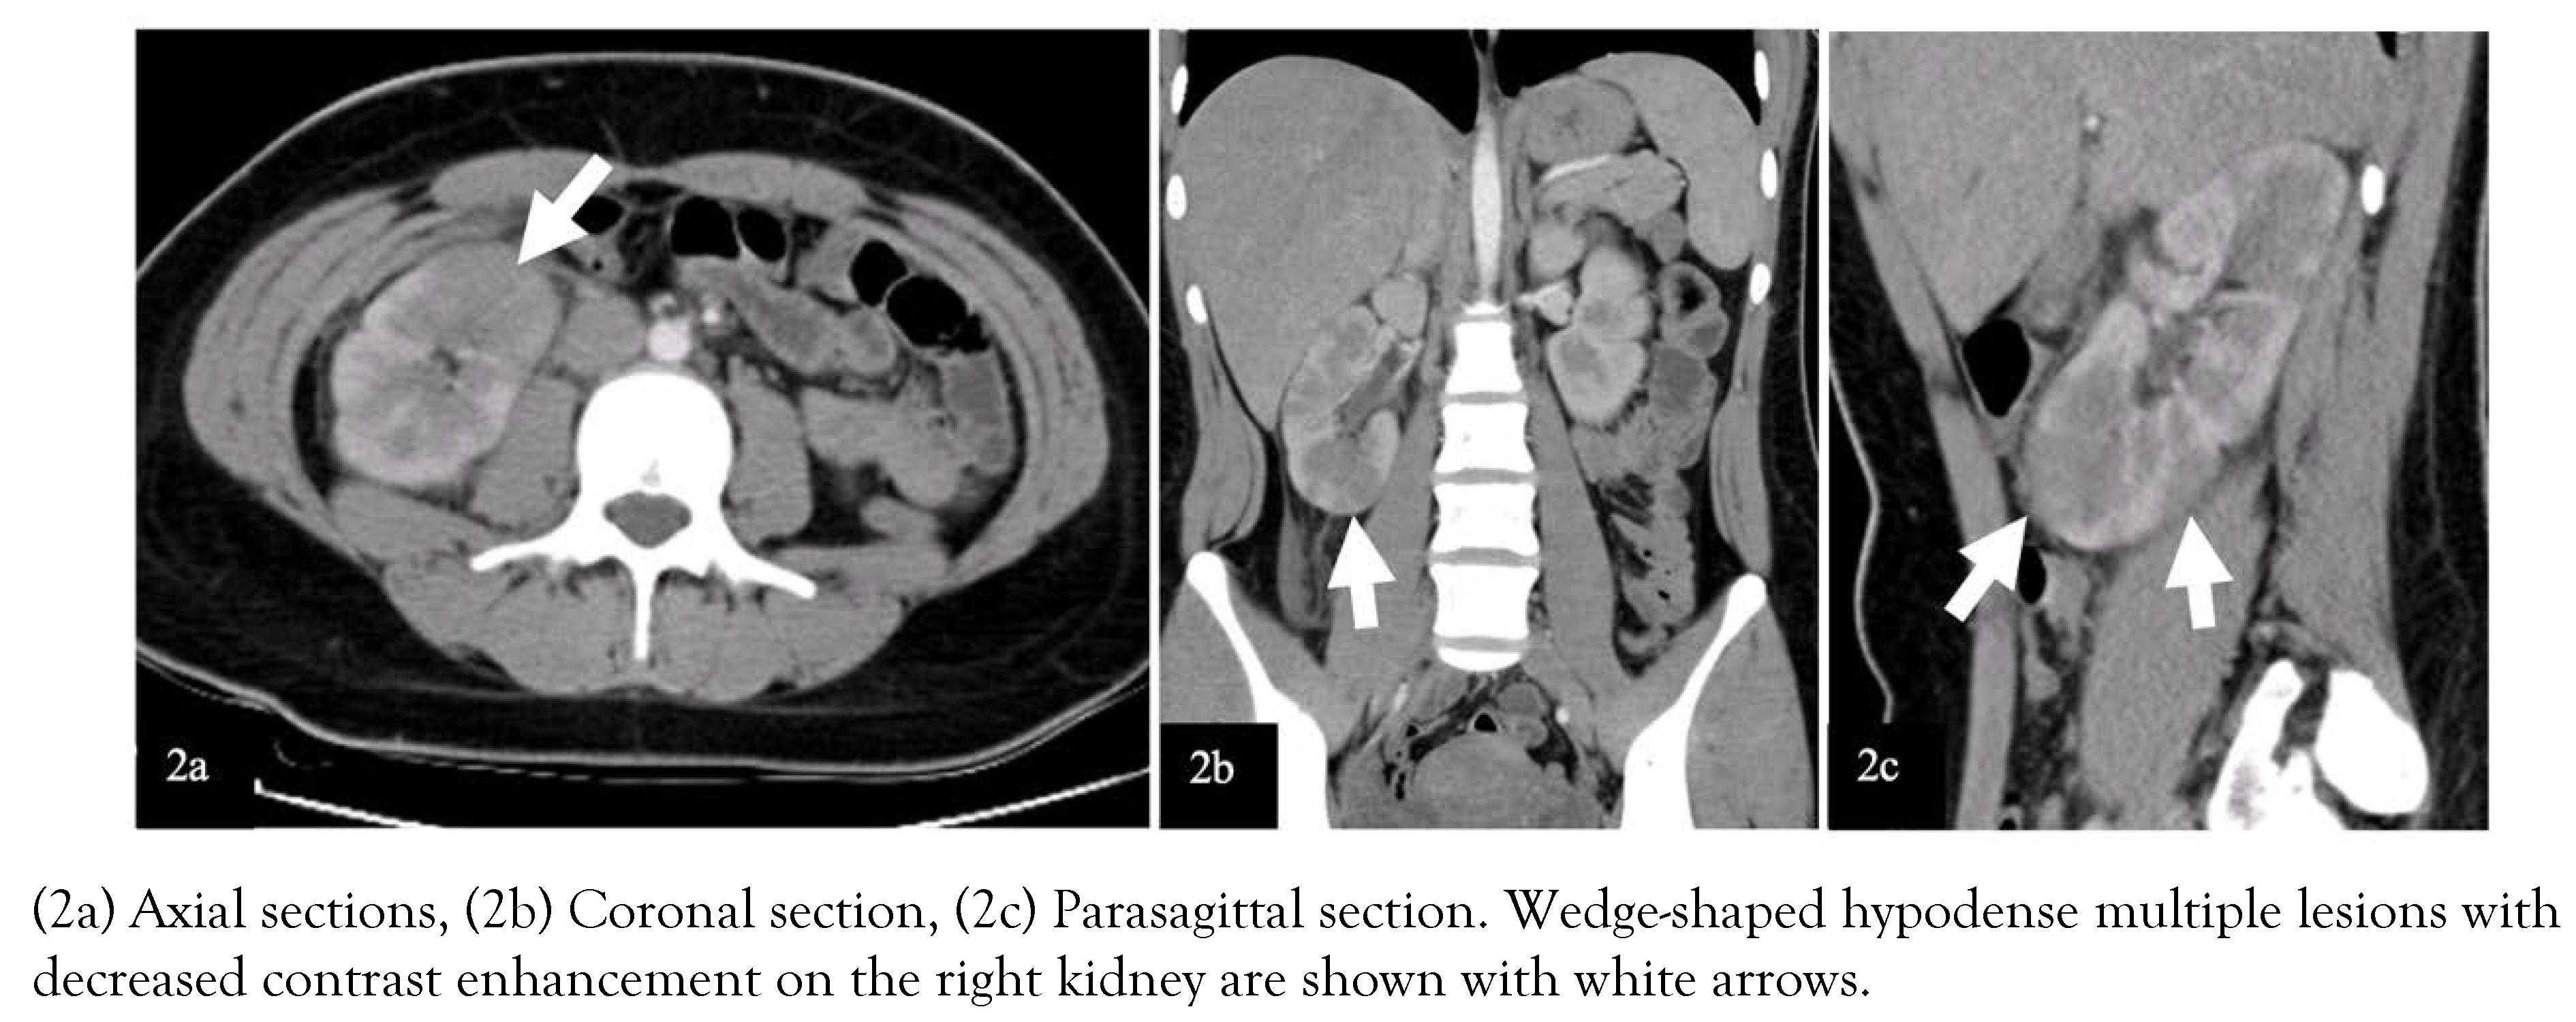

Clinical course of both cases

Due to the acute abdomen clinical finding in Case-2 and the significant CVA tenderness in both cases (bilateral in Case-1 and unilateral in Case-2), contrast-enhanced abdominal computed tomography (CT) was performed for differential diagnosis. In Case-1, nonhomogeneous hypodense mass-like lesions with decreased contrast enhancement in both kidneys were detected (Figure 1). In Case-2, a similar lesion was seen in the lower pole of the right kidney (Figure 2). Both cases were diagnosed with AFBN since these lesions were specific for it.

Costovertebral angle tenderness is one of the specific indicators for kidney pathology and is often seen in acute pyelonephritis [12]. However, it may present in other diseases such as nephrolithiasis, kidney abscess, vesicoureteral reflux, obstructive pathologies of the urinary tract, retrocecal appendicitis, retroperitoneal abscess [13]. In a patient presenting with fever and CVA tenderness, the clinician should consider first upper UTI, among other diagnoses. In selected cases, imaging techniques can be used for differential diagnosis. Herein, due to the presence of CVA tenderness, we performed contrast-enhanced CT imaging, which showed hypodense wedge-shaped kidney lesions indicating AFBN (Figure 1 and 2) [14].

Early diagnosis and effective treatment are essential in terms of preventing renal scars and morbidity such as hypertension, proteinuria, and renal failure [18]. The diagnosis of AFBN is based on radiologic examinations. In many cases, there is no finding on kidney ultrasonography (USG), although it may show nephromegaly, focal lesions with poorly defined irregular margins. Contrast-enhanced abdomen CT is the gold standard imaging technique for the diagnosis of AFBN. Herein, both cases had no finding on kidney USG. The lesions were observed on CT as the typical wedge-shaped, poorly defined hypodense lesions after contrast-medium administration [14]. The DMSA scan of the kidneys may help in the diagnosis of AFBN and the detection of renal scarring during follow-up [19]. In Case-1, the diagnosis of AFBN was supported with the DMSA scan. In Case-2, the DMSA scan in follow-up shows no scars indicating the effective treatment.

Figure 2. Images of contrast-enhanced abdominal CT of Case-2.